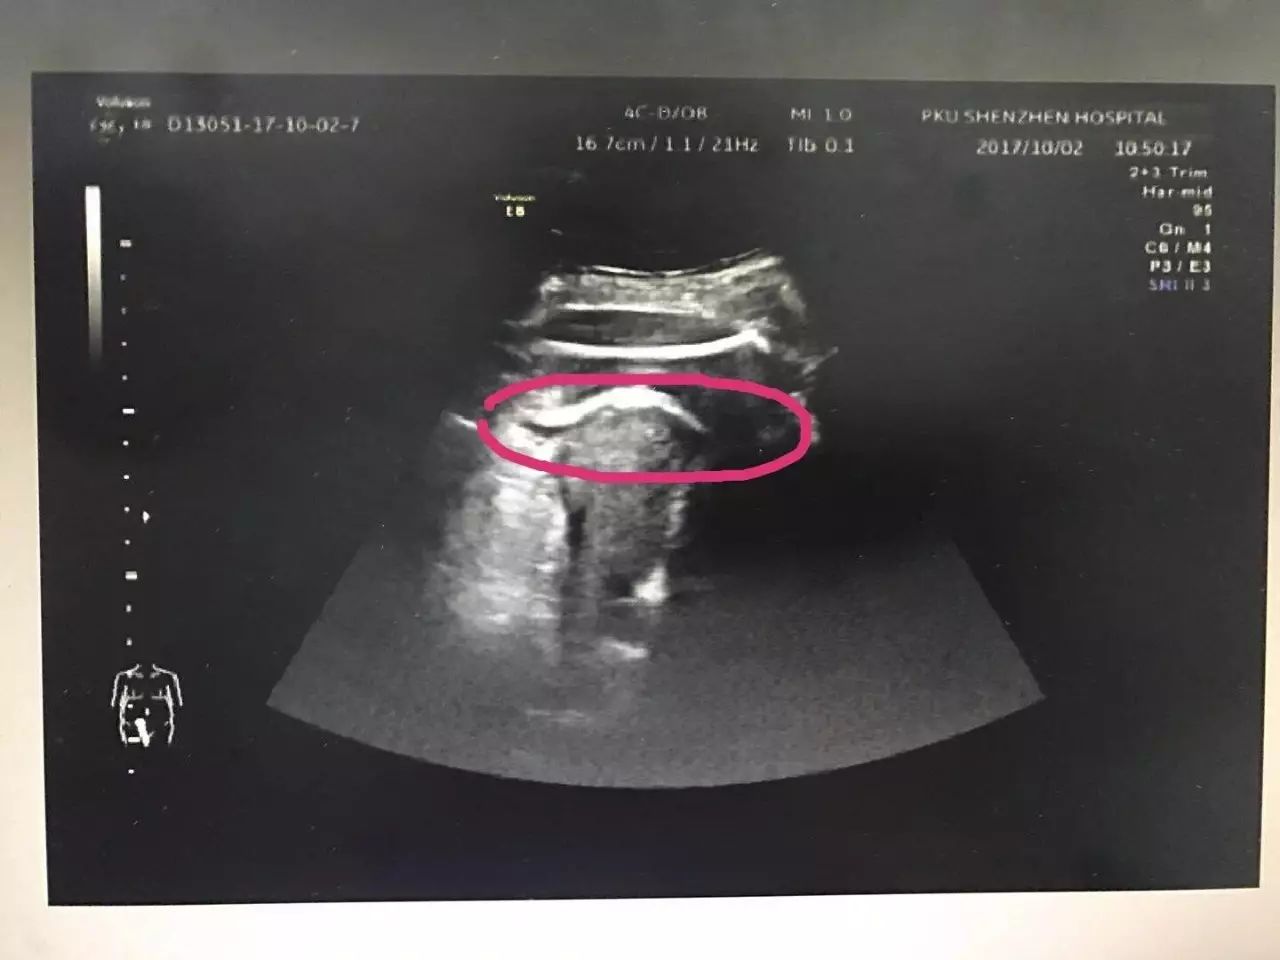

△红色圆圈处是胎儿的腿,已经伸到子宫壁外